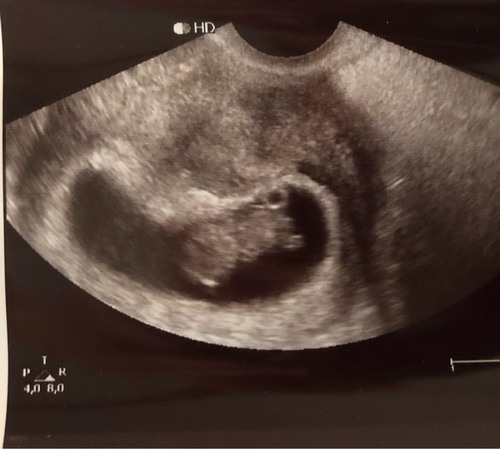

Afgelopen week de eerste echo gehad en alles was goed! Volgens mijn eigen berekening zou ik 8+4 zijn maar arts schatte het op 9+1. Kloppend hartje gezien en zagen het lichaampje zelfs al een beetje bewegen, zo leuk!

Naderhand vroeg ik mij alleen af of de vorm van de vruchtzak iets is waar ik mij zorgen over moet maken. Het is dus niet echt een ronde bol, maar wat langwerpiger met een knik erin. Hoor graag of er dames zijn die dit herkennen!

Dat ligt er aan welke dwarsdoorsnede van je lichaam op dat moment in beeld is. Wij hebben er ook vragen over, maar op een andere beeld was de vruchtzak wel rond.